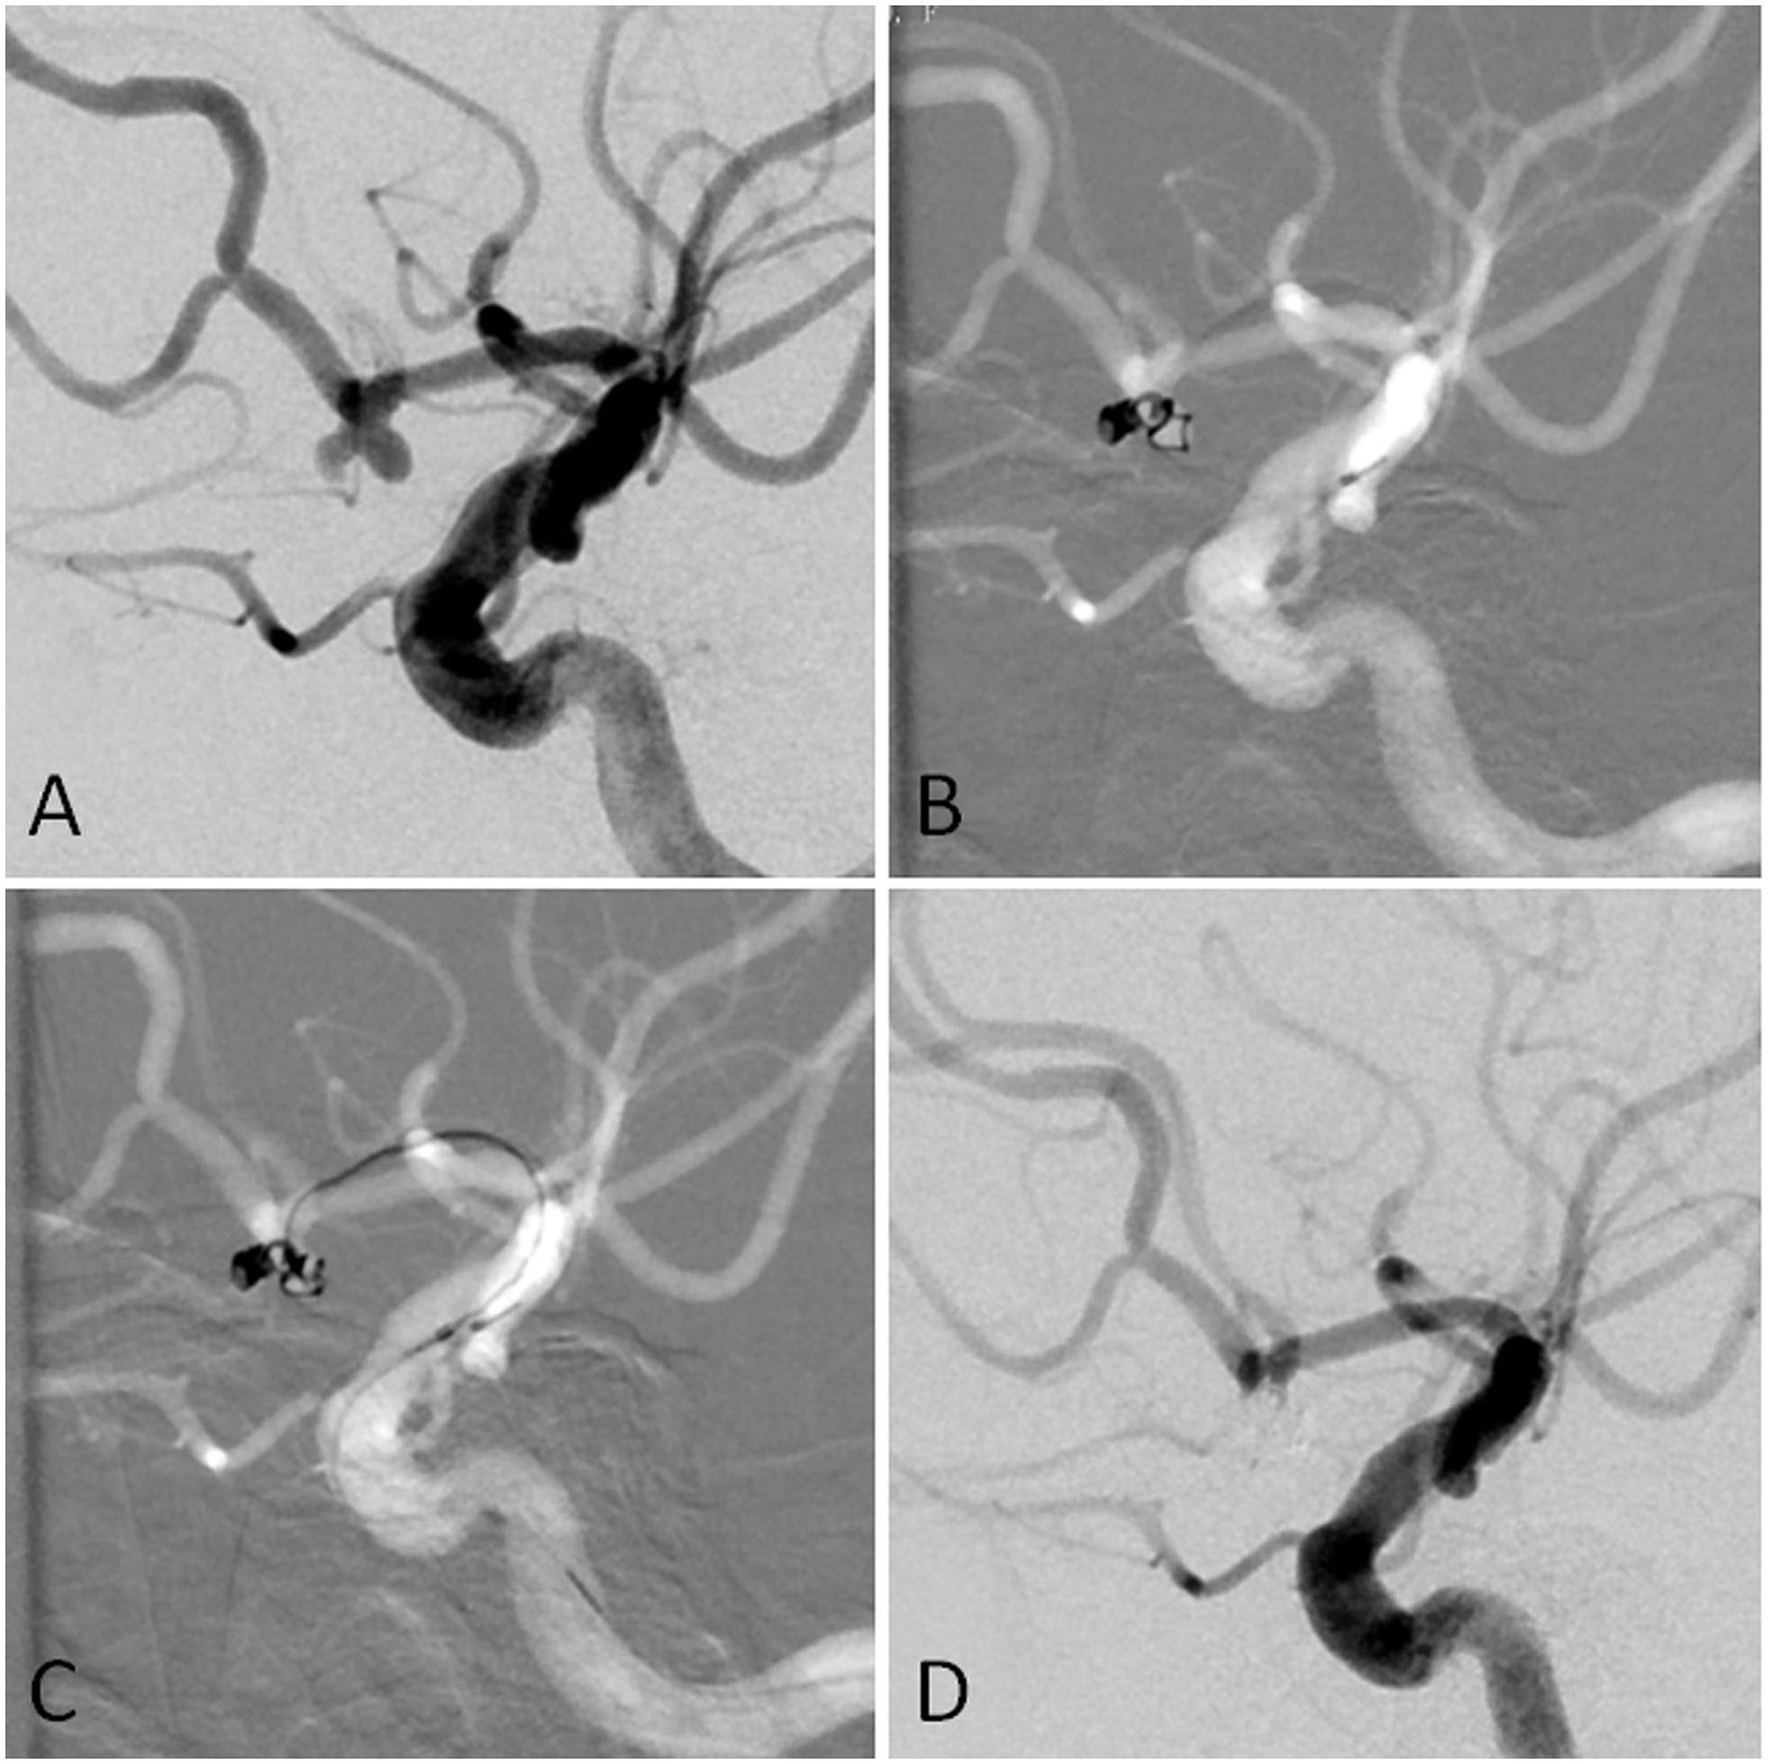

For aneurysms with a large daughter sac (Figure 1), usually one microcatheter is navigated into the daughter sac if there was no difficulty. After the first coil was fully or partially deployed, the second coil was advanced into the aneurysm through the second microcatheter, and the two coils intertwined with each other to form a stable frame. One of the coils was then detached, while the other coil remained attached to the pusher wire. Coils were then introduced through the second catheter until the aneurysm was packed as densely as possible. If blood flow was affected during this procedure, one microcatheter was removed once a stable frame was formed. For wide-necked aneurysms with lateral growth, the double-parallel framing coil technique was first attempted. To this end, two microcatheters with different shapes were consecutively or parallelly advanced into the aneurysm so that the two framing coils form a stable structure. Then, the procedure continued as described earlier. An illustrative case is presented in Figure 2. For branch-incorporated aneurysms (Figure 3), one microcatheter was placed at the orifice of the branch to prevent its occlusion, and a second microcatheter was then used to coil the aneurysm.

Figure 1. (A) The angiographic imaging showed AcomA aneurysm with the daughter sac. (B) The first was navigated into the left sac of the aneurysm. The first coil was fully advanced into the aneurysm. Part of the first coil and the microcatheter entered into the right sac in the end. (C) Another microcatheter was navigated into the aneurysm. (D) The aneurysm was completely occluded.